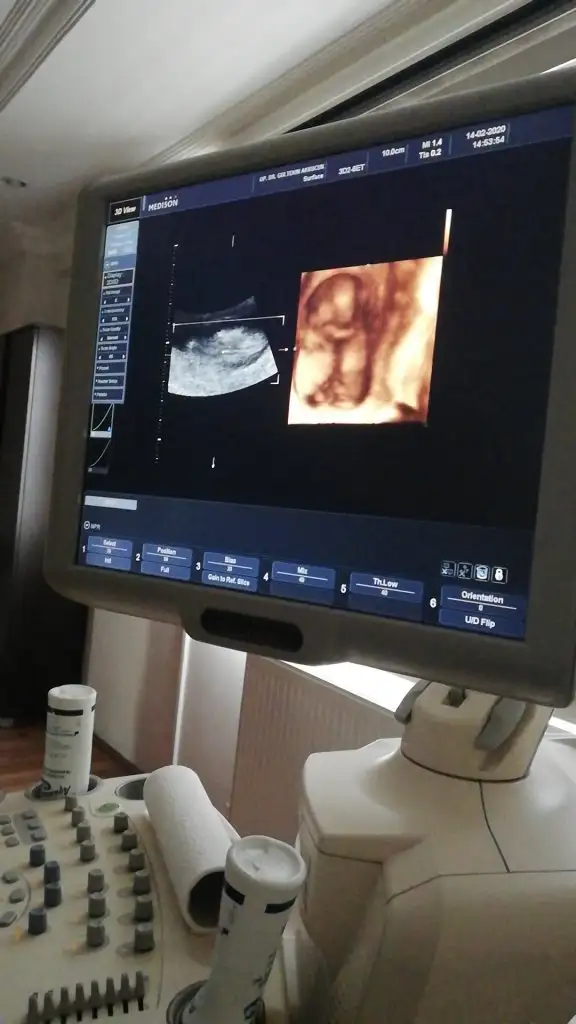

Bacak arası nubuda dik görünüyor erkek 11+2 dimi usg 12+ yada 13 olursa paylaşın A Aryaam

Canım 14+2 doktorum kıza benzetti dedim ben tereddutteyım daha önce erkeğe benzetildi ikili yltarama testinde İkra meyra

Dr. umda çok düşük ihtimal ile kız olabilir diye tahmin etti. Ama netlik için çok çok erken 2 hafta sonra netleşir dedi.

Canım ben 11+ yada 12 + nublara bakıyorum 14+2 de nub degil organı gelişmiş oluyor hadi 13 de olabilir usg dr kız dediyse kızdır cnm hmm 12 de erkek dedi diyorsun. hayırlısı olsun

Bence de kızdır artık yanılma olmuyor bu haftalarda bacak arası boştu